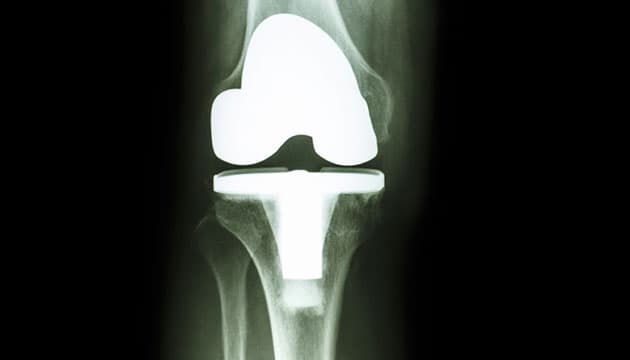

Nyt systematisk review konkluderer, at ca. 82% af helproteser i knæet og ca. 70% af delproteser holder i 25 år.

Indikationen for operation er degenerative forandringer med udtalte smerter og væsentlige begrænsninger i dagligdagen i de tilfælde, hvor konservativ behandling ikke har hjulpet tilstrækkeligt. Der findes flere forskellige typer af proteser, og generelt oplever omkring 85% af patienterne et tilfredsstillende resultat efter operation. Et nyt engelsk review baseret på over 30 studier og nationale implantatregistre søger at estimere, hvor længe hel- og delproteser kan forventes at holde. Ved indsættelse af helprotese erstattes alle ledbærende overflader i knæet med metal og plastik, og ved indsættelse af delprotese erstattes kun et enkelt ledkammer. Forfatterne konkluderer, at ca. 82% af helproteser holder i 25 år, mens den tilsvarende andel for delproteser er 70%.

Overlæge Anders Odgaard, Ortopædkirurgisk Afdeling, Gentofte Hospital, kommenterer: ”Danske resultater stemmer rigtigt godt overens med reviewets. I den seneste rapport fra Dansk Knæalloplastikregister ses det, at ca. 87% af helproteser holder i 20 år. For den almindeligste type af delproteser er holdbarheden i Danmark på ca. 72% efter 20 år. Holdbarheden er både i reviewet og i danske registre udtrykt ved den andel, der stadig fungerer efter en given årrække, f.eks. 10, 20 eller 25 år. Den gennemsnitlige holdbarhed af proteser kan ikke beregnes, da protesen for langt de fleste vil holde livet ud. Det er vigtigt at forstå, at endepunktet for en knæprotese i denne sammenhæng er en operation med udskiftning af protesen. Fraværet af en udskiftningsoperation er ikke ensbetydende med, at protesen er velfungerende. Der er flere faktorer, der har betydning for holdbarheden og funktionen af en knæprotese, heriblandt protesetypen, den kirurgiske teknik, forhold hos patienten og – ikke mindst – indikationen for operation. En operation med indsættelse af en knæprotese, del- eller helprotese, vil for langt hovedparten af patienter medføre en stor forbedring af livskvalitet. En proteseholdbarhed på 70-85% efter 20-25 år er i dette lys glædeligt. Det er vores mål stadig at forbedre både funktionen og holdbarheden af knæproteser”.